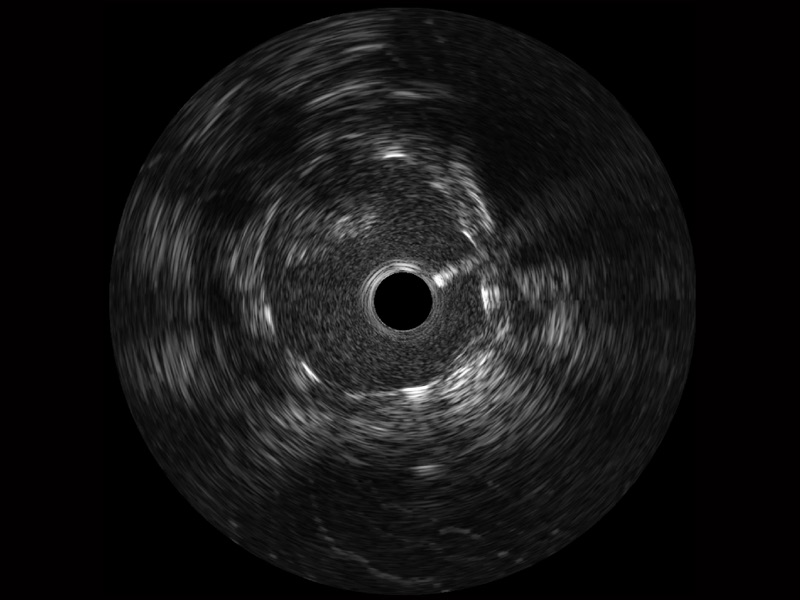

DB中国旗舰官方网站宽频IVUS图像

传统IVUS图像

对比传统IVUS导管成像,DB中国旗舰官方网站宽频IVUS图像的近场支架梁显影更细腻,远场中膜外血管仍清晰可辨,兼顾远中近,兼顾分辨力与穿透深度